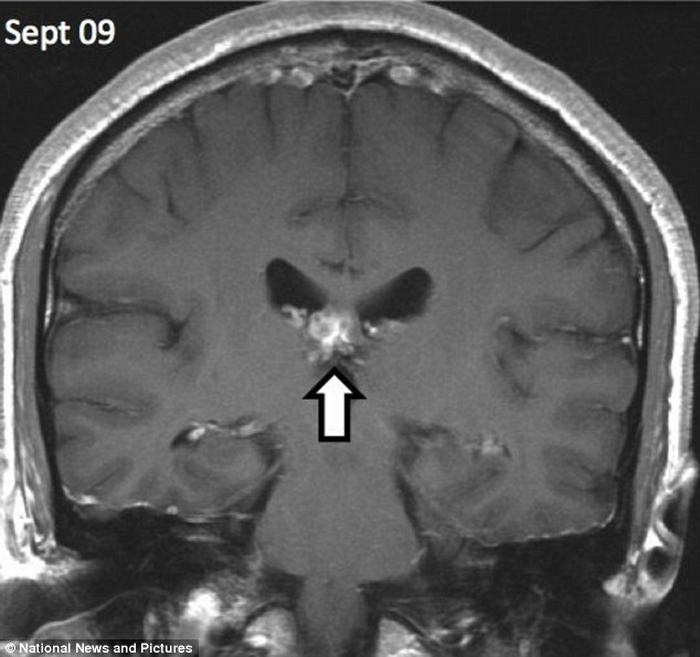

| Con sán đã ‘du lịch’ khoảng 5cm từ phía bên phải sang bên trái của não người đàn ông này trong suốt 4 năm. |